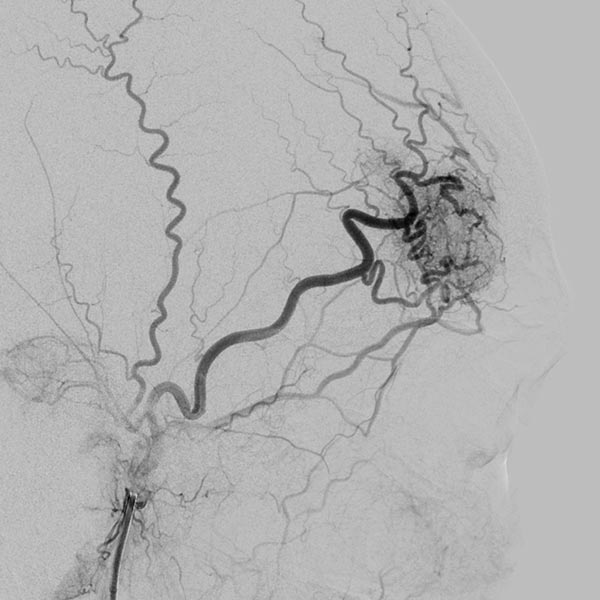

DSA-Bild mit Darstellung des gesamten arteriellen Einstroms, des Nidus und des venösen Abstroms der AVM vor der Embolisation. Die Angioanatomie der hier noch unbehandelten AVM ist klar erkennbar.

Die Abschlussangiographie nach Injektion in die rechte Arteria carotis externa zeigt den kompletten Verschluss des Nidus der arteriovenösen Malformation. Durch die Subtraktionsdarstellung erscheint der Cast hier weiß.